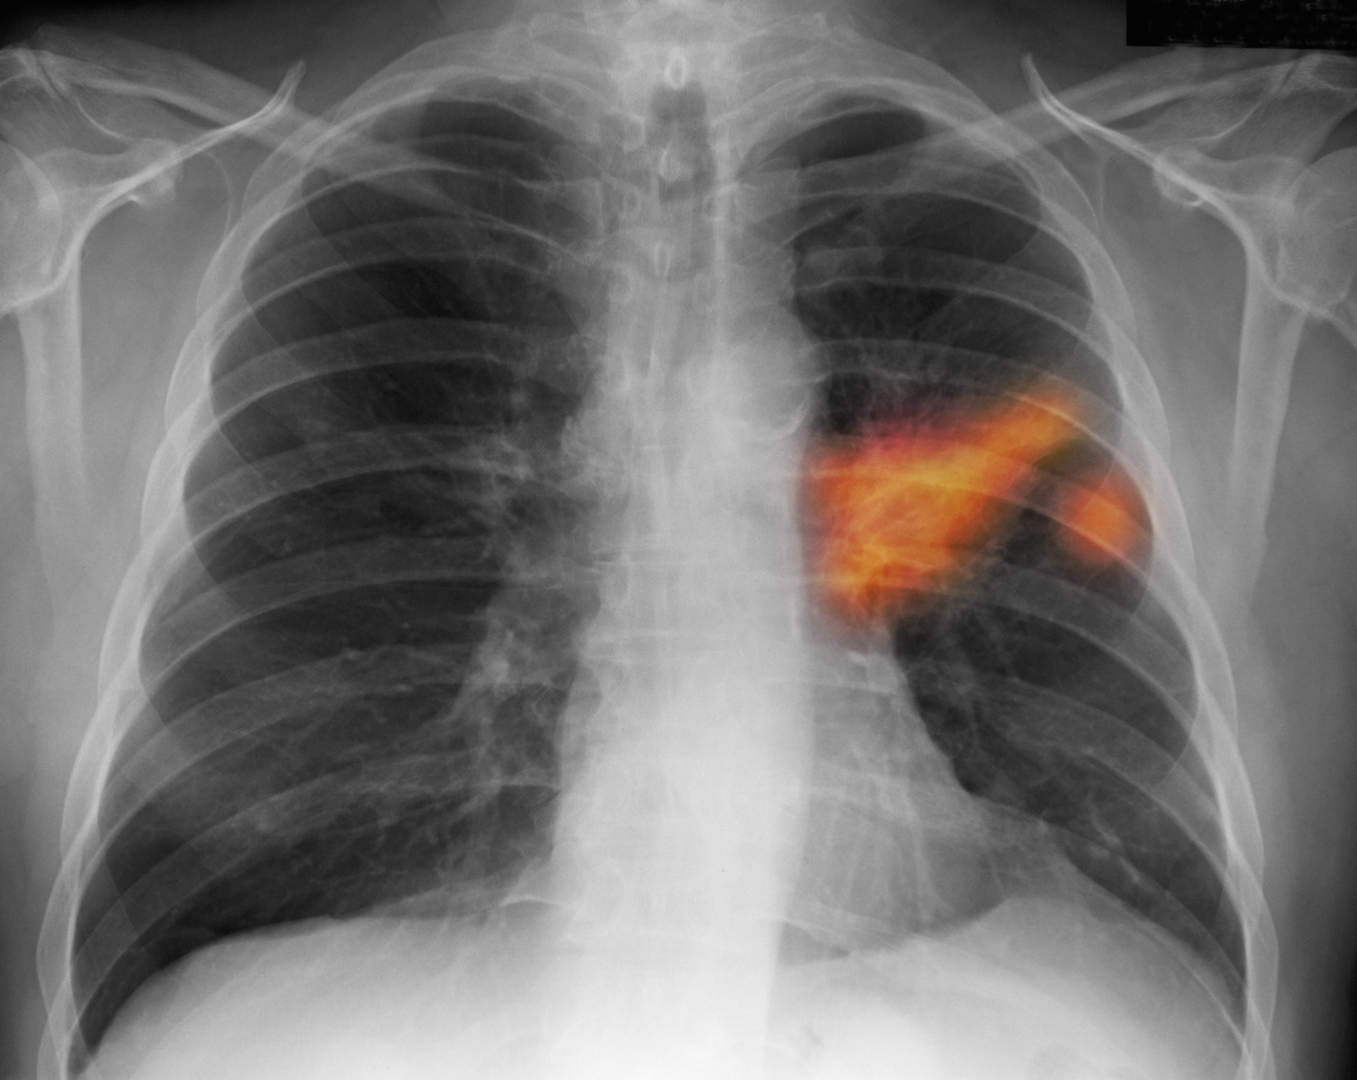

العلماء يحددون آلية تربط "كوفيد-19" بسرطان الرئة

كشفت دراسة دولية أن فيروس كورونا قد يترك آثارا صحية طويلة المدى تتجاوز المرحلة الحادة من المرض....